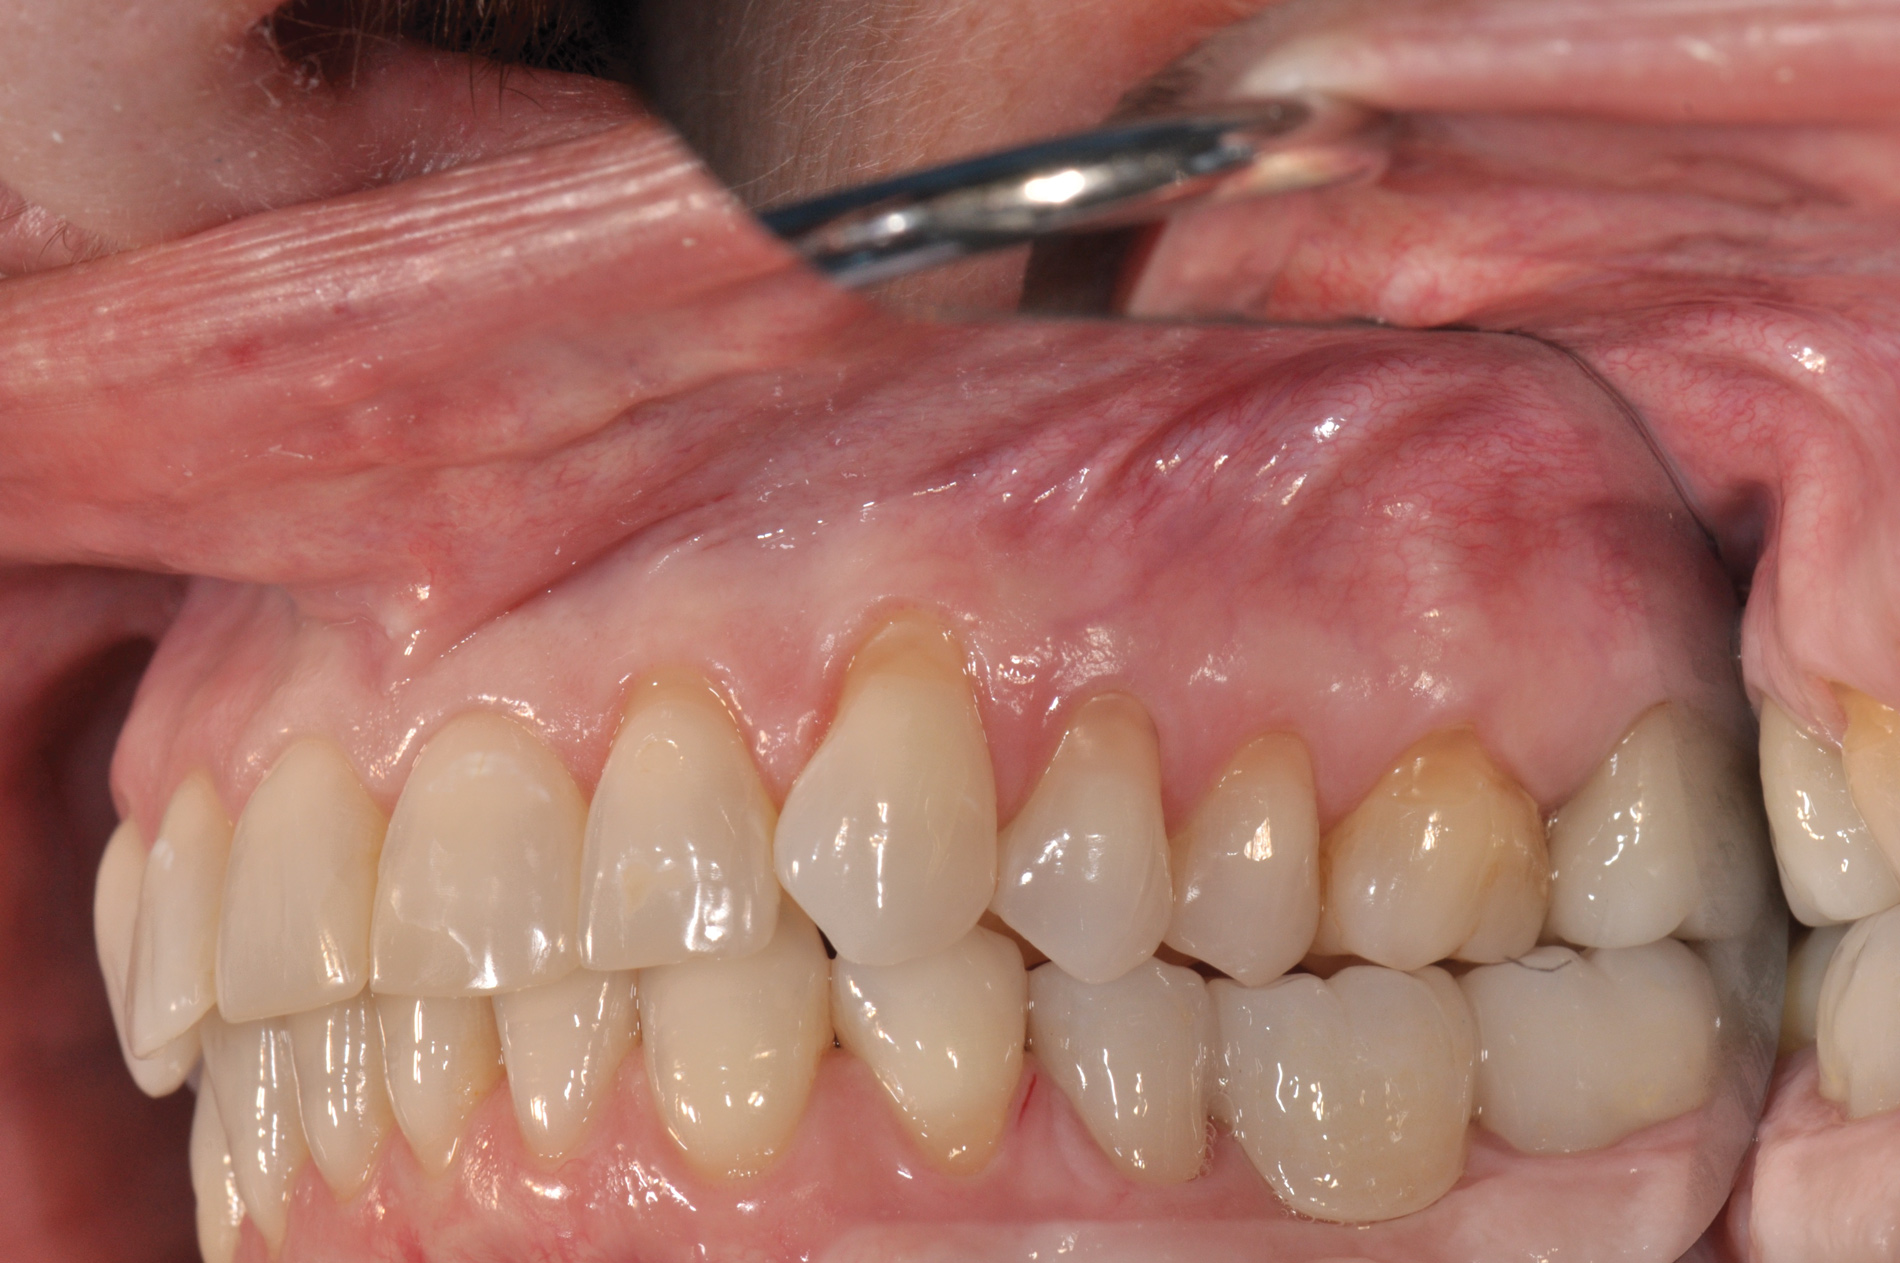

(6. THROUGH 8.) Vertical orientation jig used to position and lute prefabricated PMMA bridge to prepared temporary abutments with orientation jig.

Figure 6

Figure 7

Figure 8